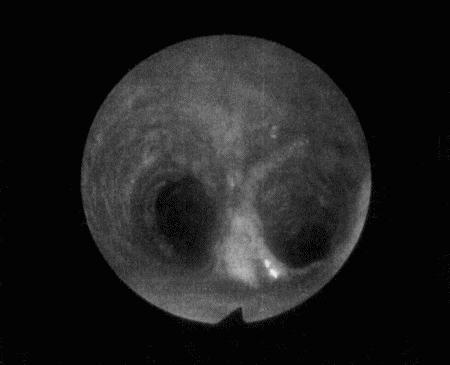

Фиг. 3.12.

Эндоскопическая картина бифуркации рогов матки у суки, наблюдаемая на 23 день после родов